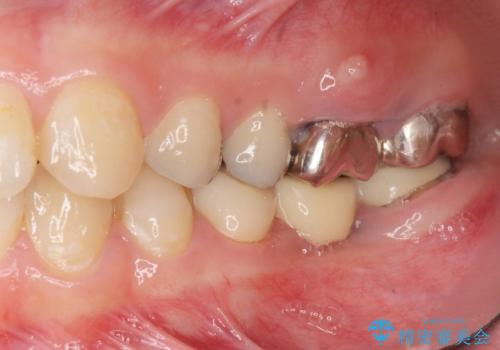

インプラント・セラミック・矯正治療を含む包括歯科診療

- 「地元の歯医者にずっと通っているが、どんどん歯が悪くなる。時間とお金がかかってもいいので徹底的に歯を治したい。」

、と総合的な歯科治療を希望されて来院されました。

虫歯や咬合関係・歯槽骨の吸収・根尖病変・歯の欠損・複合的な問題を一つずつ解決し、

安定した噛み合わせの構築・歯ブラシのしやすい環境の整備・歯内歯周の感染除去・造骨を伴うインプラント治療

を行い、長期的な予後を見込める口腔内環境を確立、整備して行きます。